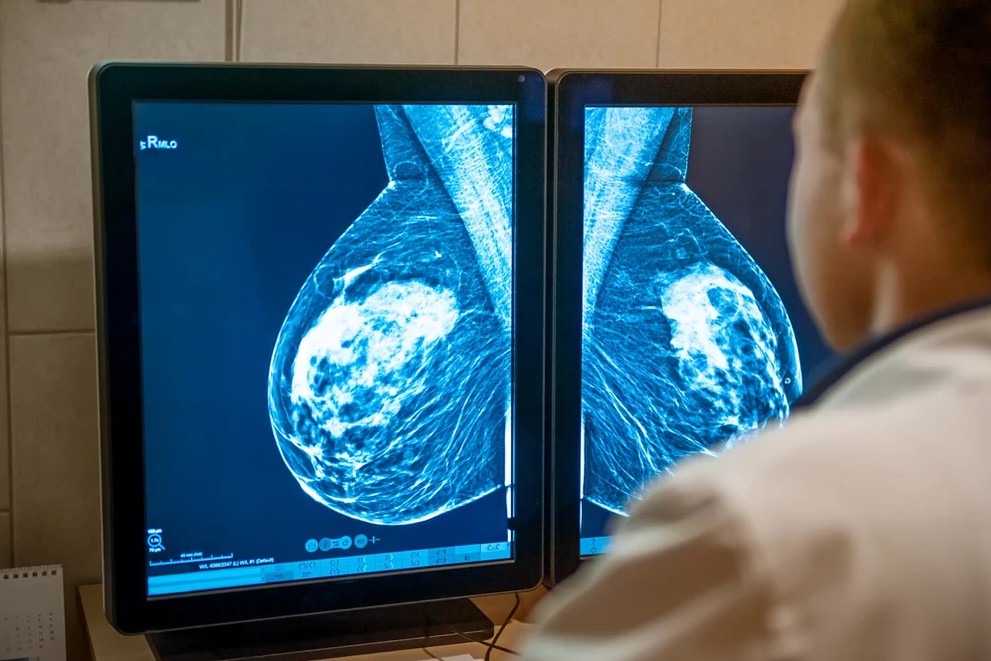

Ung thư vú giai đoạn 0 được hiểu như thế nào?

Ung thư vú giai đoạn 0 hay còn gọi là giai đoạn sớm nhất, đây là giai đoạn các bác sĩ coi là tiền ung thư. Giai đoạn này ung thư không xâm lấn và ít tiến triển hơn giai đoạn 1.

Ở giai đoạn này, các tế bào ung thư bất thường chỉ xuất hiện trong các ống tuyến sữa hoặc tiểu thùy tuyến vú và chưa xâm lấn vào các mô xung quanh

- Ung thư biểu mô ống tại chỗ (Ductal carcinoma in situ - DCIS). DCIS là xuất hiện trong hầu hết các trường hợp khi nói về ung thư vú giai đoạn 0. Các tế bào bất thường vẫn còn trong ống dẫn sữa và không ảnh hưởng đến các mô mỡ chiếm phần lớn vú. Không rõ nguyên nhân và hầu hết người bệnh không có bất kỳ triệu chứng nào, mặc dù có thể nhận thấy một khối u hoặc chảy máu từ núm vú. Các tế bào bất thường có thể hoặc không trở nên xâm lấn và bắt đầu lan rộng. Không có cách nào để dự đoán liệu điều này sẽ xảy ra hay không.